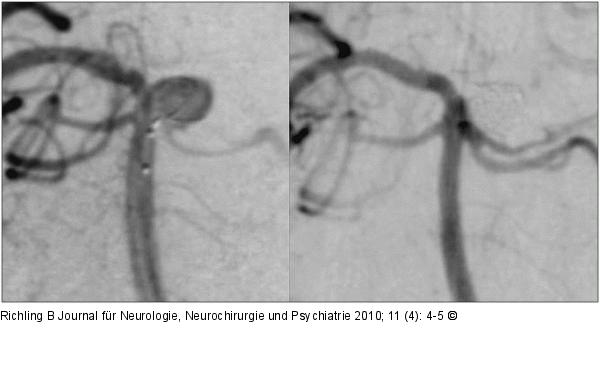

Abbildung 3: Aneurysma Aneurysma der Arteria cerebelli superior links. Links: Einbringung des ersten Coils. Rechts: Nach Beendigung des Eingriffs. |

Aneurysma der Arteria cerebelli superior links. Links: Einbringung des ersten Coils. Rechts: Nach Beendigung des Eingriffs. |